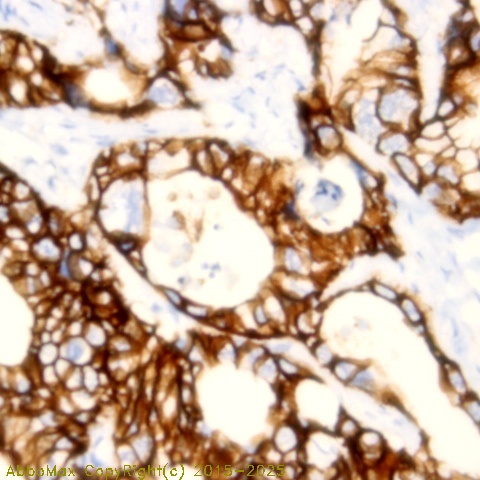

EpCam

"EpCam, the epithelial cell adhesion molecule, is a carcinoma-associated antigen and a member of a family that includes at least two type I membrane proteins. EpCAM is a monomeric membrane glycoprotein that is expressed in most normal human epithelium and carcinomas. It is overexpressed in a variety of carcinomas and is, therefore, a potential target for the visualization and therapy of human solid tumors. The antigen is being used as a target for immunotherapy treatment of human carcinomas. Mutations in this gene result in congenital tufting enteropathy."

IHC

2-10 µg/ml

Applications: IHC(P), WB